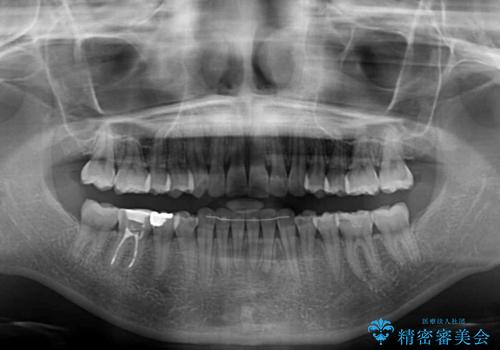

- 上下前歯の突出感とデコボコを気にして来院された患者様です。

インビザラインによる上下歯列の側方拡大と後方移動、IPR(歯と歯の間を削る)にるスペースの獲得により歯列を整えることとしました。

骨格的な左右差があったため、上下の正中を合わせることができませんでした。

骨格の差は改善できないため、奥歯の咬み合わせに物足りなさを感じましたが、奥歯の咬み合わせによる不自由はなく、口元の突出感も改善することができました。